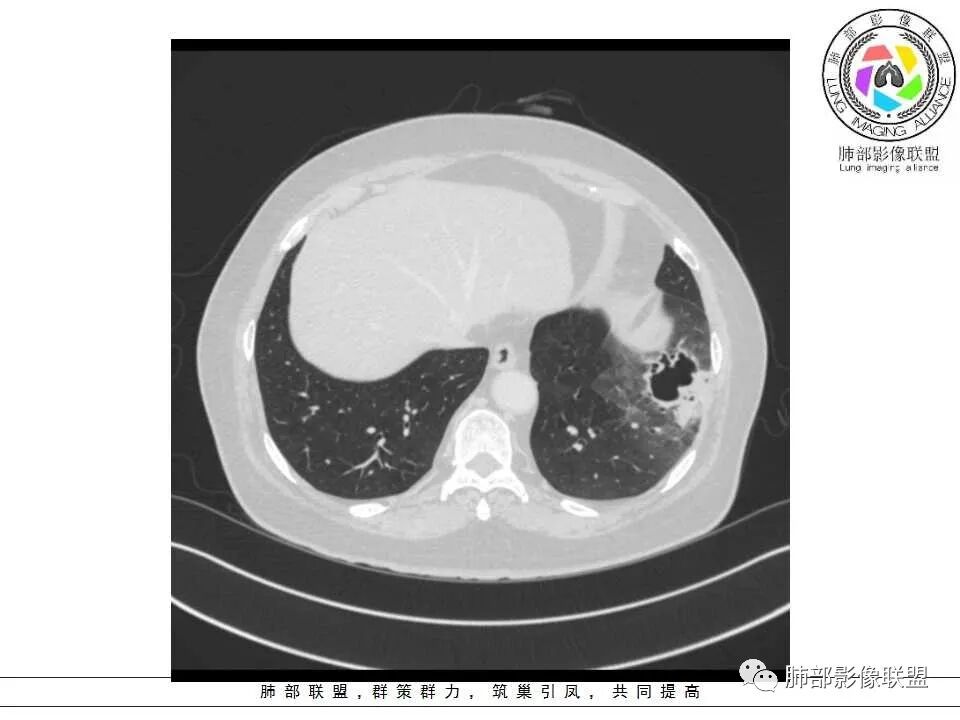

病灶分两部分

周围大片GGO

中央囊实性病变

患者老年女性,2月前受凉后出现发热,咳嗽咳痰,痰量增多,无咳血,病程较长,临床症状无明显好转并,近2日咳嗽加重,痰量增多,为黄白痰,无发热,无乏力、盗汗,无胸痛、胸闷,无头晕、头痛,无恶心、呕吐。

影像特点:

1、左肺下叶外基底段不规则囊腔样病灶,囊腔内有条形影及血管穿行。

2、囊壁薄厚不均匀,稍显僵硬,有壁结节(对应边缘分叶等)、结节强化明显。

以上两条几乎将肺囊肿彻底排除在外,且高度怀疑新生物!

3、灶周环以大范围磨玻璃影,非常均匀,没有重力分布趋势,分叶状,边界隐约可变。

4、冠状位部分层面可见支气管在囊腔边缘截断。

囊腔型肺癌主要为腺癌,少数为鳞癌。

本例囊腔性病灶尽管腔壁稍显僵硬,壁结节凸显,但女性患者,灶周明显磨玻璃晕,都强烈提示为囊腔性腺癌。

病理粘液腺癌确乎意外,非常罕见!

大范围磨玻璃影可以符合粘液腺癌。机制包括分泌黏液的癌细胞沿肺泡壁生长以及含肿瘤细胞的黏液成分沿气道飘散种植等。囊腔形成推测肿瘤等成分形成小支气管的活瓣阻塞所致。

周围磨玻璃影不支持炎性渗出,没有沿气道分布,边缘较清楚;未形成肺泡结节,出血也不符合,且患者临床无咯血。